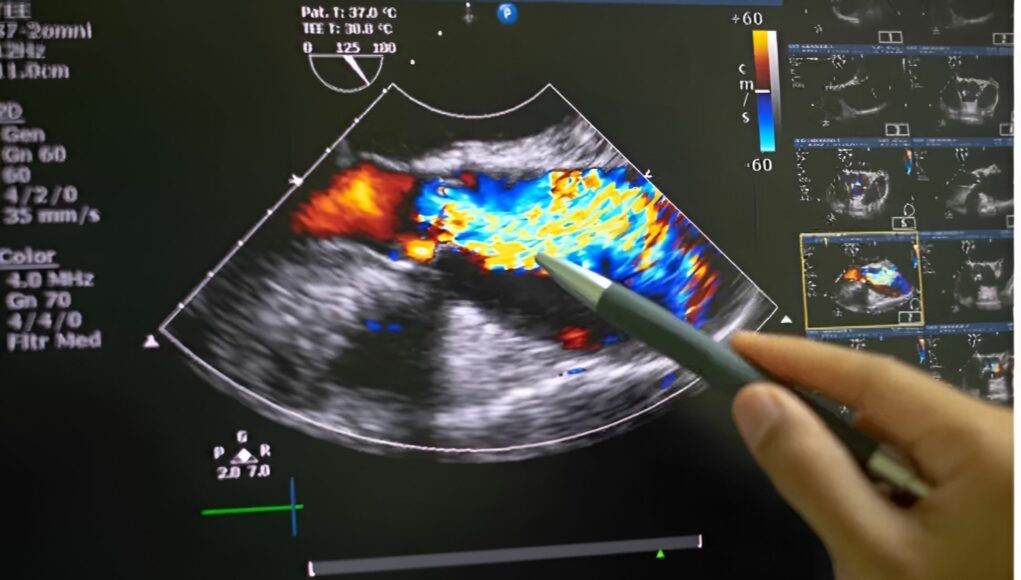

L’ecografia addominale è un esame diagnostico, altamente informativo, non invasivo, indolore basato sugli ultrasuoni. Il principio è lo stesso che usano i pipistrelli per orientarsi, vengono emessi dei suoni che rimbalzando sugli ostacoli che trovano nella loro strada, il muro di una caverna per un pipistrello, o i nostri organi nel caso di un ecografia. Una volta ritornati alla sonda, che scivola dolcemente sulla pelle dopo l’applicazione di un gel, gli ultrasuoni producono un’immagine che permette di vedere perfettamente all’interno del nostro corpo. L’esame si svolge in circa 15-30 minuti, data la quantità di informazioni che raccoglie è un tempo veramente esiguo, richiede però una leggera preparazione come altri esami, ad esempio potrebbe essere richiesto di presentarsi all’esame a digiuno, di assumere carbone vegetale al fine di ridurre i gas intestinali, o di recarsi all’esame con la vescica piena permettendo di visualizzare meglio la vescica. é un esame tenuto sempre in considerazione data la sua velocità, versatilità e ripetibilità senza rischi.

Essendo l’addome una zona del corpo dove si concentrano molti organi, una sola ecografia è in grado di fornire una panoramica approfondita e individuare svariate patologie definendosi come un esame utile e importante per la diagnostica e la prevenzione.